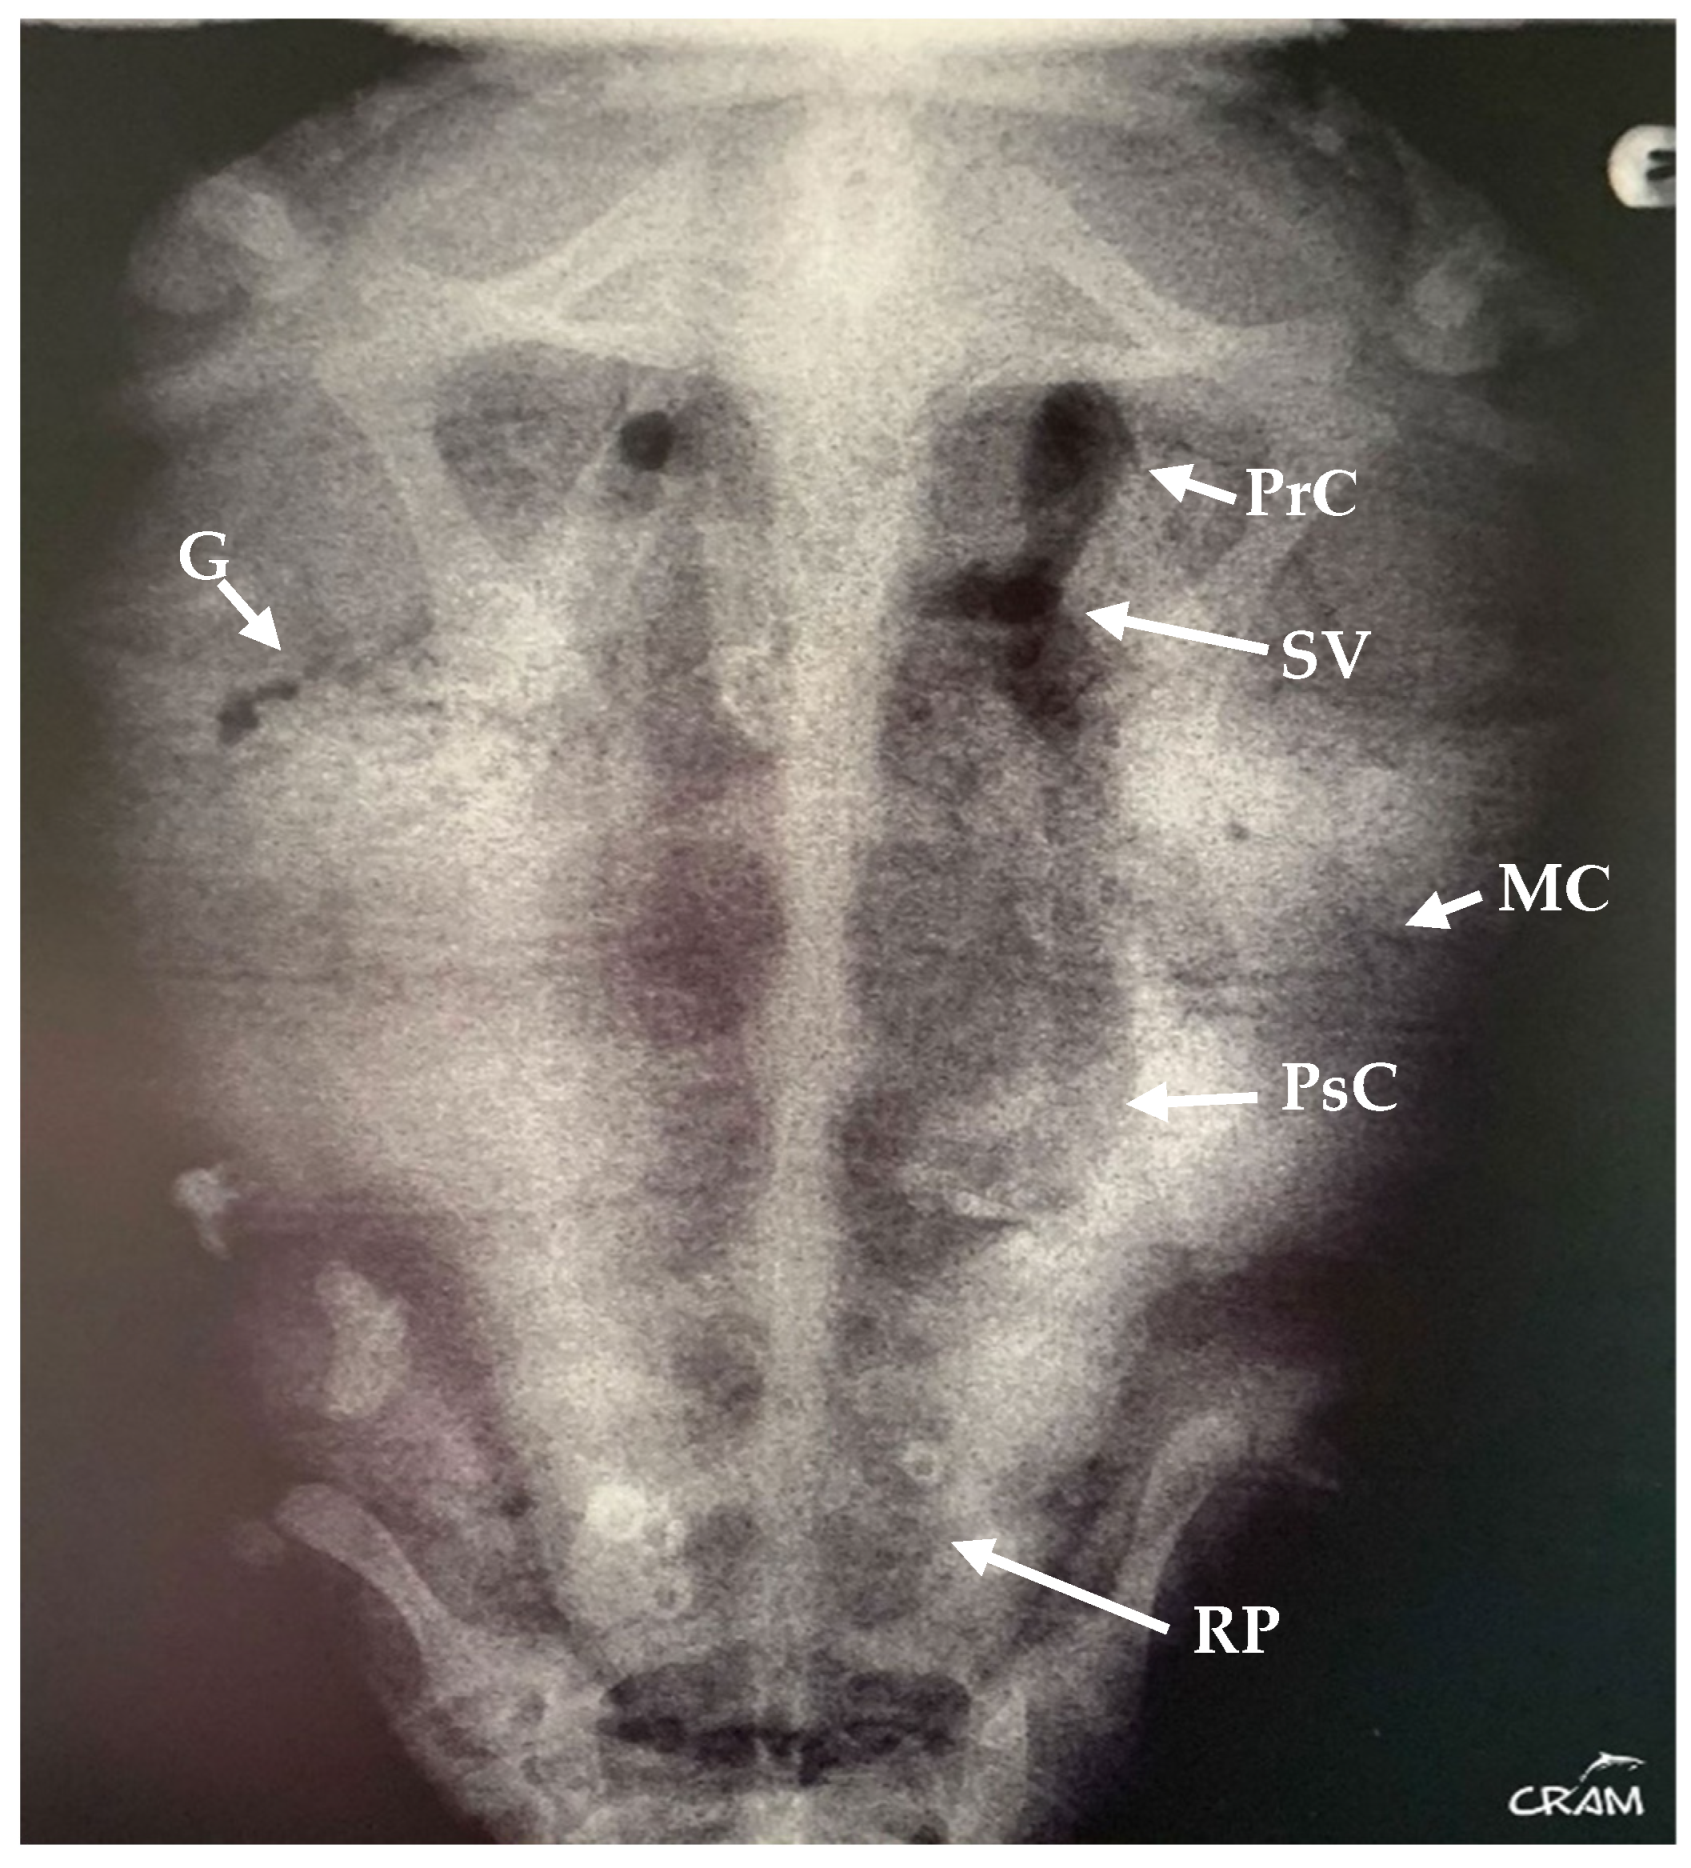

In March 2019, the same turtle, then identified as CC19/037, was accidentally captured by a trawler ship and presented moderate-to-severe gas embolism (Figure 1), based on the classification proposed by García-Párraga et al. (2014). DCS was diagnosed by radiography and response to hyperbaric chamber treatment. An injury at the level of both fifth lateral (costal) scutes of the carapace (Figure 2) was also present. The treatment for DCS was hyperbaric air at 1.6 atm pressure inside a hyperbaric chamber and 5 mg kg−1 enrofloxacin, IM q 48 h for 15 days, with debridement and curettage of the wound. The turtle was released from the beach in May 2019.

Figure 1.

Dorsoventral radiograph of CC19/037 with GE of moderate-to-severe degree. Gas is evident in precava (PrC) and postcava (PsC) veins, sinus venosus (SV), gastric vessels (G), marginocostal vessels (MC), and renal portal vessels (RP).